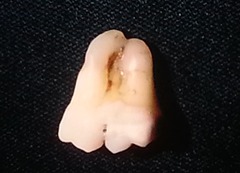

chronic hyperplastic pulpitis

-Red or pink nodule protruding from the pulp chamber or a tooth with a large open carious lesion (usually molars)